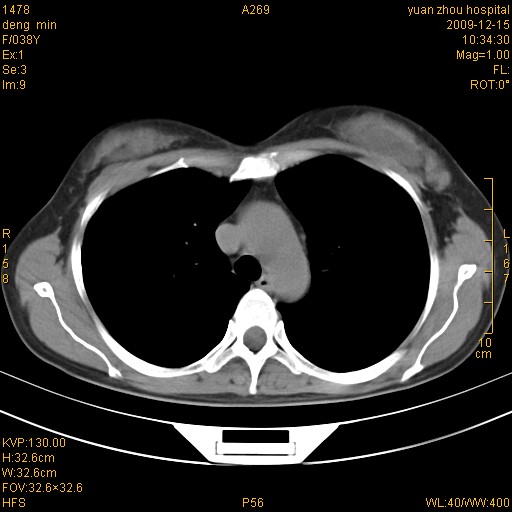

标题: CT23919:F38Y 咳嗽月余 [打印本页]

标题: CT23919:F38Y 咳嗽月余

右肺中下叶、左肺上叶舌段及左肺下叶支气管扩张合并感染。